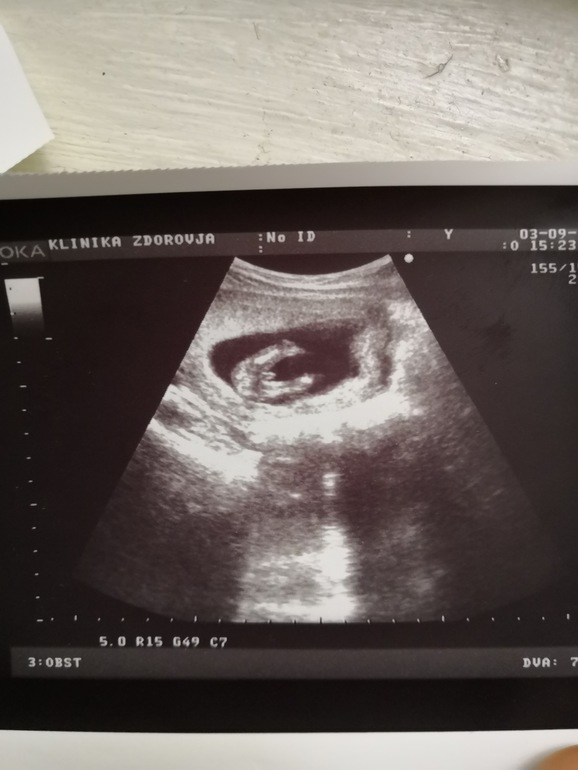

это мы в 4 недели, тогда чуть отстаивали от срока по месячным,по мес была 6 неделя и сколько то дней,